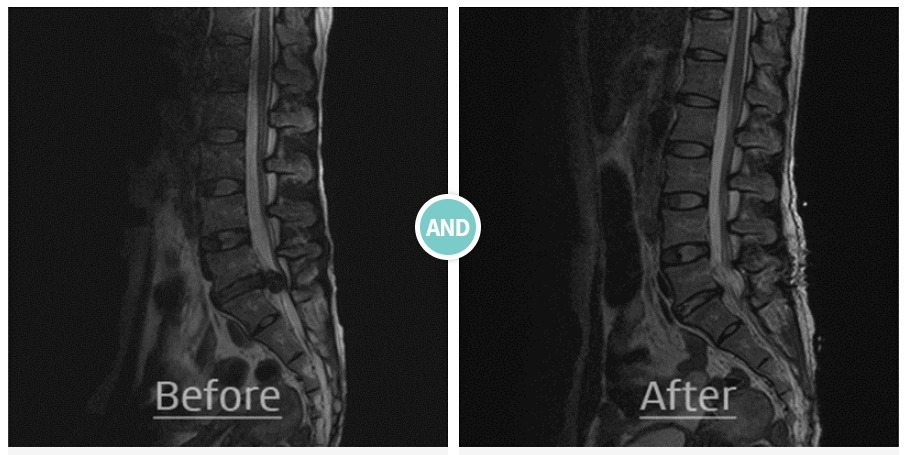

허리디스크_수핵탈출증_1.jpg 인체 척추에서 연골 추간판이 탈출한 모습(좌). 수술 후 모습(우) [이미지 출처: 용인분당 예스병원]

허리디스크 치료방법에는 신경 감압 및 디스크 제거술, 내시경 디스크 제거술 등의 수술 치료와 약물, 보조기 및 물리치료 등의 비수술 보존적 치료법이 있다. 척추질환은 수술로만 개선된다는 선입견이 많지만, 허리 디스크 환자의 약 75~80%는 특별한 치료 없이도 증상이 호전될 수 있어 대부분 비수술적인 치료방법이 먼저 권장된다.